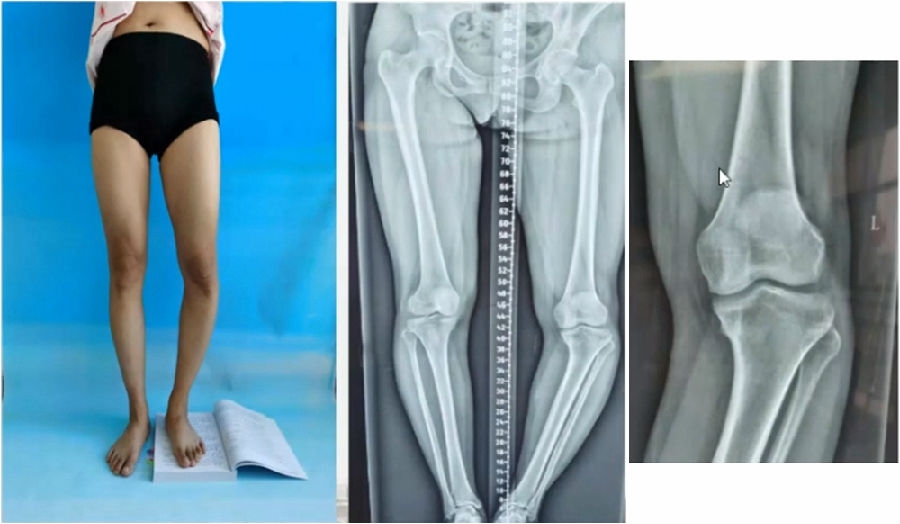

典型病例,女性,56岁,农民右膝内翻18度。

术前影像

典型病例,男性,65岁,农民,双膝内翻16度。

典型病例,女性,35岁,农民,左膝内翻、短缩、内旋。

术前

典型病例2,男性,52岁,双膝疼痛,低磷佝偻病,复合畸形。